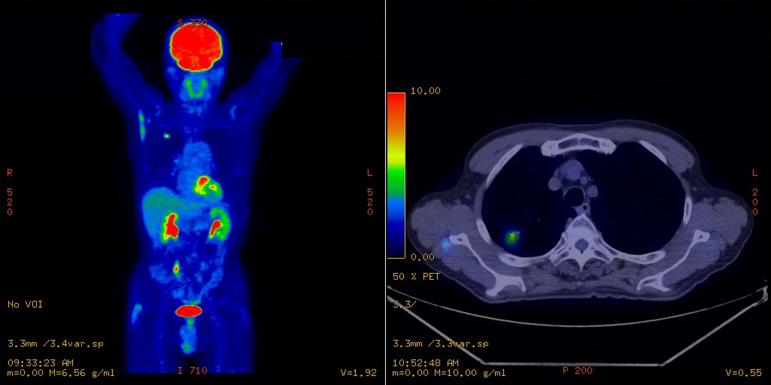

PET:Positron Emission Tomography (陽電子放出断層撮影)はブドウ糖ががんに集まる性質を利用して全身を一度に調べることができます。

CT:Computed Tomography(コンピューター断層撮影)はX線を使って体を輪切りにしたような詳細な画像をつくります。

PETは代謝の異常を、CTは形状の異常をみることができ、それぞれに得手・不得手があります。この両方の検査を組み合わせることで、がんの転移の状態を高い精度で調べることができます。

肺がんのステージ分類においてPET単独装置とPET/CT合体装置の成績比較をしたところ、PET/CT合体装置のほうが優れていたという報告があります。また、従来は骨への転移を調べるために骨シンチグラグラフィという検査が用いられていましたが、PET/CTで代替が可能なため、骨シンチグラグラフィを省略することができます。